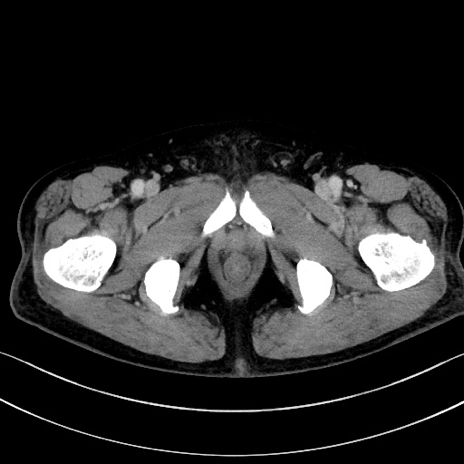

症例15(横断像)

【症例】70歳代男性

【主訴】腹痛

【現病歴】今朝から腹痛あり。全体的に痛い。特に左上の方。排ガスが今日はない。冷や汗が出る。

【既往歴】直腸癌術後

【身体所見】左側腹部〜上腹部に圧痛あり。腹膜刺激症状明らかなではない。軽度反跳痛。左下腹部に術後瘢痕あり。

【データ】WBC 7700、CRP 0.02